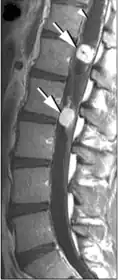

Гемангиобластомы в области позвоночного канала

Гемангиобластомы в области позвоночного канала обычно располагаются интрамедуллярно (в спинном мозге), но могут находиться и экстрамедуллярно (вне спинного мозга). В 50 % они поражают грудной отдел и в 40 % шейный. Так как гемангиобластомы представляют собой богатоваскуляризированные новообразования, то их клиническая манифестация может дебютировать субарахноидальным кровоизлиянием[12][26].

В большинстве случаев гемангиобластомы в области позвоночного канала представляют собой солитарное образование, однако в 20 % могут наблюдаться множественные новообразования (как правило, при болезни Гиппеля — Линдау). Приблизительно в половине случаев (43—60 %) образуются сирингомиелические полости. Кисты могут достигать больших размеров, располагаясь выше и ниже солидного узла опухоли[26][27][28].

При спинальной ангиографии определяется богато васкуляризированный узел новообразования с крупными приводящими артериями. В связи с этим целесообразным является при подозрении на гемангиобластому проведение селективной ангиографии. Катетеризация артерий, которые кровоснабжают опухоль, может быть использована для одновременной предоперационной эмболизации приводящих сосудов[26].

Компьютерная томография с контрастным усилением позволяет хорошо визуализировать гемангиобластому. На МР томограммах узел опухоли имеет гипо- или изоинтенсивный сигнал на Т1-взвешенных томограммах и гиперинтенсивный — на Т2-взвешенных. Кистозные полости имеют сигнал, близкий по своим характеристикам к ликвору. Узел опухоли хорошо накапливает контрастные вещества. При этом интенсивность сигнала от стенок кист обычно не повышается[26][28].

Хотя гемангиобластомы на магнитно-резонансных томограммах и не имеют признаков, которые с полной достоверностью свидетельствовали бы именно о наличии данного новообразования, можно выделить несколько характерных признаков[26]:

- сочетание больших кистозных образований с небольшим солидным узлом;

- наличие расширенных и извитых сосудов в субарахноидальном пространстве спинного мозга;

- множественность поражения при болезни Гиппеля — Линдау.